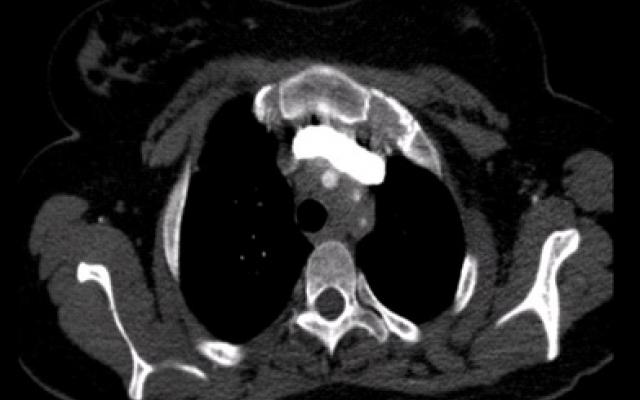

Een 23-jarige vrouw kwam op de polikliniek Interne Geneeskunde. Wegens een toename in de frequentie van haar migraine-aanvallen sinds 6 maanden had de huisarts een bètablokker voorgeschreven. Vervolgens had patiënte klachten gekregen van duizeligheid en zwarte vlekken voor haar ogen bij opstaan uit zittende of liggende houding, na fysieke inspanning en bij overgang van koud naar warm. Verder had zij last van tintelingen en een witte verkleuring van de vingers van de linkerhand bij blootstelling aan koude. Eenmalig had zij een kortdurende woordvindstoornis. Patiënte was met de bètablokker gestopt en gebruikte nu alleen de anticonceptiepil. De pulsaties van de…